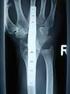

4 424 K. Perner Fall 4: Bei der 69-jährigen Patientin wurde 1990 eine Hüft- TEP links mit zementiertem Titanschaft implantiert. Drei Jahre später kam die Frau mit einer periprothetischen Fraktur und ausgelockertem Schaft an unsere Abteilung (Abb. 12). Intraoperativ fand man in der Frakturzone ausgeprägte pathologische Veränderungen des Knochens, wie bei einer Osteomalazie. Obwohl das proximale Femurende weitgehend zerstört war (Abb. 13), ließ sich dieser Casus mit einem Plus-SLR-Schaft sanieren. Dieser Schaft, von dem nur das distale Drittel im intakten Knochen verankert ist, fungiert proximal als Stützgerüst für die Knochenfragmente, die um ihn ancercliert wurden. Die Abb. 14 zeigt das Ausheilungsergebnis 118 Monate postoperativ. Abb. 12 Fall 5: Am zog sich die 86-jährige Patientin bei liegenden Hüft- und Knieimplantaten eine periprothetische Fraktur des linken Oberschenkels distal der Prothesenspitze zu (Abb. 15). Abb. 13 Abb. 15 An einer traumatologischen Abteilung wurde am eine Plattenosteosynthese durchgeführt (Abb. 16). Wegen der fehlenden medialen Abstützung kam es am zum Plattenbruch (Abb. 17). Bei der erfolgten Reosteosynthese am wurde wiederum eine Plattenosteosynthese, die durch eine Titankrallenplatte und drei Titan-Bandcerclagen verstärkt wurde, durchgeführt. Die unzureichende mediale Abstützung blieb unverändert (Abb. 18). Abb. 14 Schon 4 Monate später kam es, wie zu erwarten, erneut zum Bruch des Osteosynthesematerials (Abb. 19).

6 426 K. Perner Abb. 22 Abb. 21 Trotzdem wurden daraus keine Konsequenzen gezogen und am wieder eine Plattenosteosynthese, diesmal kombiniert mit zwei Titankrallenplatten und vier Titanbandcerclagen, gemacht. Auch durch die zusätzlich angelagerten Spongiosachips konnte die medialseitige Abstützung verbessert werden (Abb. 20). Nach weiteren 4 Monaten kam die Patientin mit einem erneuten Ermüdungsbruch des Osteosynthesematerials an unsere Abteilung. Bei der Revision führten wir eine sparsame Resektion der Knochenstümpfe durch, um medialseitig eine corticale Abstützung zu erreichen. Danach wurden die Fragmente mit je einer ventral und lateral angelegten AO-Platte unter Kompression verschraubt (Abb. 22). Dies führte schon wenige Monate nach der Revision zum knöchernen Durchbau der Fraktur. Die Abbildung 23 zeigt das Ausheilungsergebnis 24 Monate postoperativ. Abb. 23